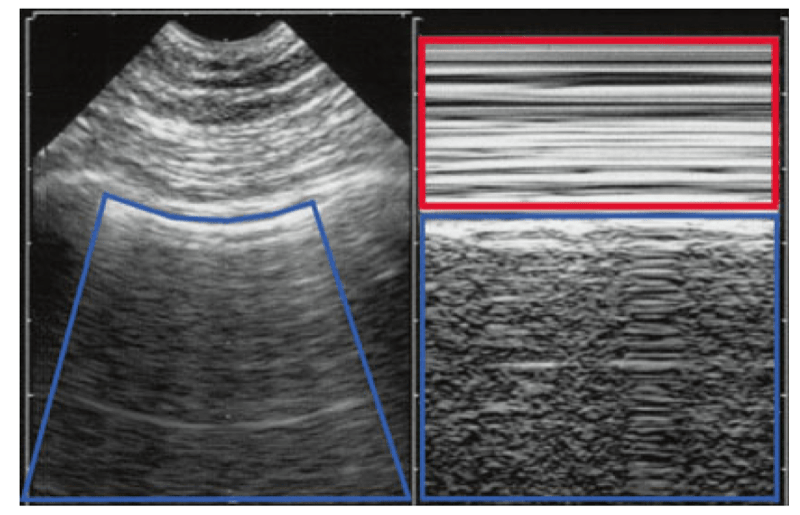

6. फेफड़ों के अल्ट्रासाउंड का मानकीकरण: कीज़ स्पेस

बुनियादी परिघटनाओं को मानकीकृत करना आसान बनाने के लिए, हमने M-मोड द्वारा उत्पन्न एक आभासी स्थान परिभाषित किया है। फुफ्फुस रेखा एक ऊपरी आयत और एक निचले आयत को अलग करती है। फुफ्फुस रेखा द्वारा नीचे की ओर (ऊपर और पार्श्व में छवि की सीमाओं द्वारा) सीमित इस ऊपरी आयत को कीज़ स्पेस (लिंडा कीज़, कोलोराडो की CEURFer से) कहा गया है।अंजीर 3) की के अंतरिक्ष में जो कुछ घटित होता है वह फेफड़े के लिए सतही है।

चित्र 3 की और मर्लिन का स्थान। बाईं ओर (वास्तविक समय में), मर्लिन का स्थान (नीले रंग में), जो फुफ्फुस रेखा के नीचे की स्थिति को दर्शाता है (पसलियों की परछाईं को छोड़कर)। दाईं ओर (एम-मोड), फुफ्फुस रेखा द्वारा अलग किए गए दो स्थान, फेफड़ों के अल्ट्रासाउंड की किसी भी छवि में परिभाषित किए जा सकते हैं। (1) एक ऊपरी आयत, की का स्थान (लाल रंग में), एक आभासी स्थान, जो फुफ्फुस रेखा के ऊपर की स्थिति को दर्शाता है। (2) एक निचला आयत, जिसे एमएम-स्थान को सरल बनाने के लिए कहा गया है, जो फुफ्फुस रेखा के नीचे और नीचे जो दिखाई देता है उसे मूर्त रूप देता है। इस महत्वपूर्ण बिंदु पर ध्यान दें: दोनों छवियां (बाएं और दाएं) एक-दूसरे के बगल में सख्ती से रखी गई हैं। इससे क्षेत्र को मानकीकृत करने में मदद मिलेगी। अब मर्लिन के स्थान (ए-लाइन) की सामग्री का विवरण थोड़ा अपरिपक्व होगा; की स्पेस (श्वास कष्ट का अभाव) और एमएम-स्पेस (फेफड़ों का खिसकना) डेटा से भरपूर हैं: ए-प्रोफाइल का आधार, योजनाबद्ध रूप से एक सामान्य फेफड़े की सतह

शांत श्वास में, की के स्थान को एक स्तरीकृत पैटर्न के रूप में वर्णित किया जा सकता है। श्वास कष्ट के दौरान, दुर्घटनाएं अंदर दिखाई देती हैं। बस एक महत्वपूर्ण विवरण पर ध्यान दें: चमगादड़ के चिह्न का उपयोग करके वास्तविक समय की छवि पर बिना किसी भ्रम के फुफ्फुस रेखा पूरी तरह से परिभाषित है। हमारी 1992 की मशीन (अंतिम अद्यतन 2008) का उपयोग करते हुए, फुफ्फुस रेखा बिल्कुल उसी स्तर पर है, भ्रम की कोई गुंजाइश नहीं, दाहिनी एम-मोड छवि पर, बिना किसी विलंब के जैसा कि लगभग सभी लैपटॉप मशीनों में देखा जाता है। इसका मतलब यह है कि, दाहिनी छवि पर फुफ्फुस रेखा की खोज के लिए, व्यक्ति को बस उस बिंदु तक जारी रखना है जहां यह दिखाई देती है (एम-मोड शूटिंग लाइन में, माना जाता है कि बीच में) दाहिनी छवि तक। आधुनिक मशीनों को इस तरह से कॉन्फ़िगर न करना LUCI के सिद्धांत N 1 का उल्लंघन होगा: सरलता।

7. फेफड़ों के अल्ट्रासाउंड का मानकीकरण: एम-मोड-मर्लिन स्पेस

इस अवधारणा को स्पष्ट करने के लिए हमें एक और इकाई परिभाषित करनी होगी। की स्पेस को M-मोड छवि के ऊपरी वर्ग के रूप में परिभाषित किया गया है। निचला वर्ग एक लेबल के योग्य है। चूँकि यह मर्लिन स्पेस (वास्तविक समय अवधारणा) से मेल खाता है, इसलिए हम इसे "M-मर्लिन स्पेस" नाम देंगे। LUCI में कोई भी M-मोड छवि दो स्पेस से बनी होती है, ऊपर की स्पेस और नीचे M-मोड-मर्लिन स्पेस, दोनों को प्ल्यूरल लाइन को मूर्त रूप देने वाली रेखा द्वारा अलग किया जाता है।